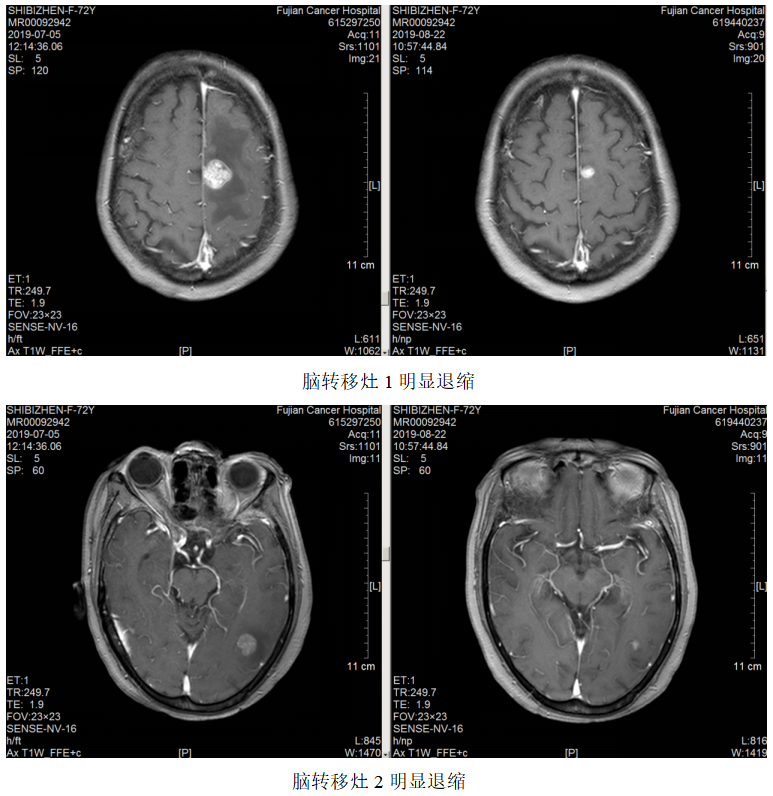

局部放疗:2019.7.23~2019.8.7予脑转移灶调强放疗DT3900CGy/13F。

疗效评估:PR。

维持治疗:2019.11.6~2022.03.02予方案“卡培他滨+曲妥珠单抗q3w”维持治疗。

2021.5.18开始患者因经济原因改予汉曲优治疗至今,肿瘤进一步退缩,疗效评估PR。